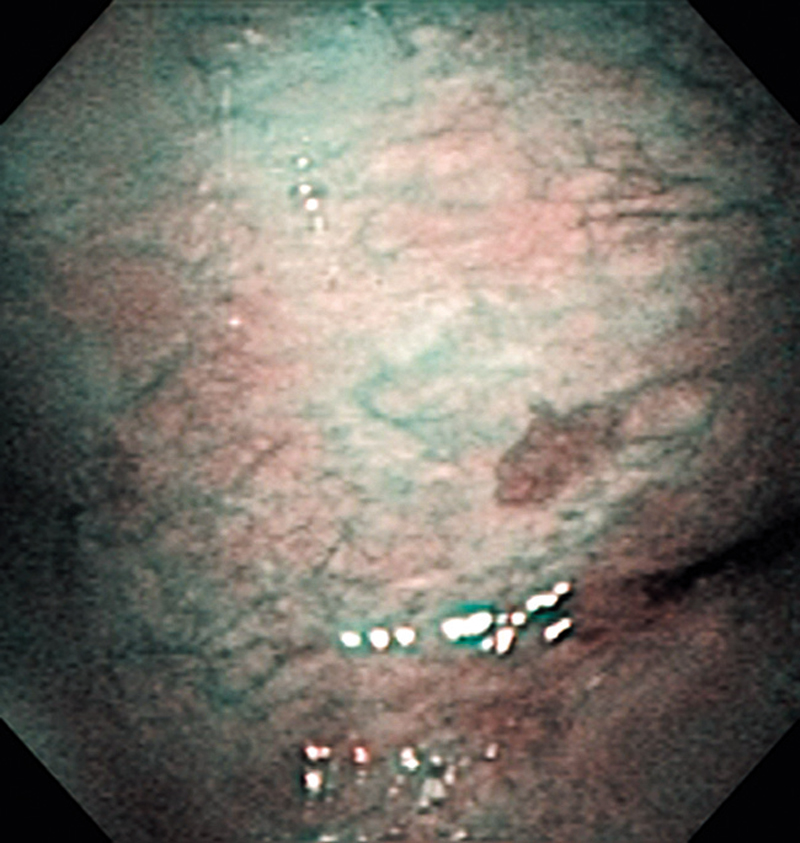

The lesion was detected in the oropharyngeal posterior wall in a laryngopharyngoscopic NBI examination during follow-up after treatment of a carcinoma in the floor of the mouth.

It was recognized under NBI as a lesion with a brownish area, and the close-up view additionally showed scattered brown dots. In the conventional white light image, the same area was seen as a reddening lesion.

The lesion was 5 x 3 mm and located on the back of the soft palate, and was diagnosed as a carcinoma in situ.